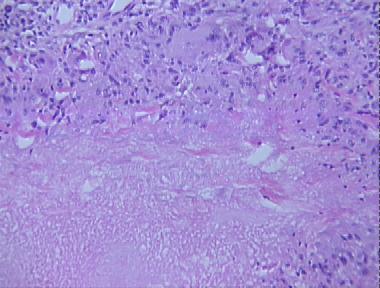

tertiary syphilis

Histologic Features